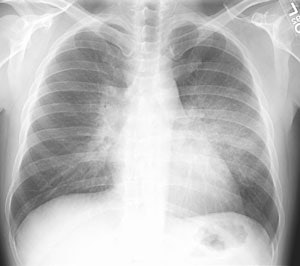

Alveolar Proteinosis:

The patient presented for evaluation of progressive shortness of breath. The CXR demonstrated bilateral perihilar infiltrates producing an appearance of pulmonary edema. HRCT exam revealed central areas of ground glass attenuation with underlying septal thickening producing a "crazy paving" appearance. Click images to enlarge.